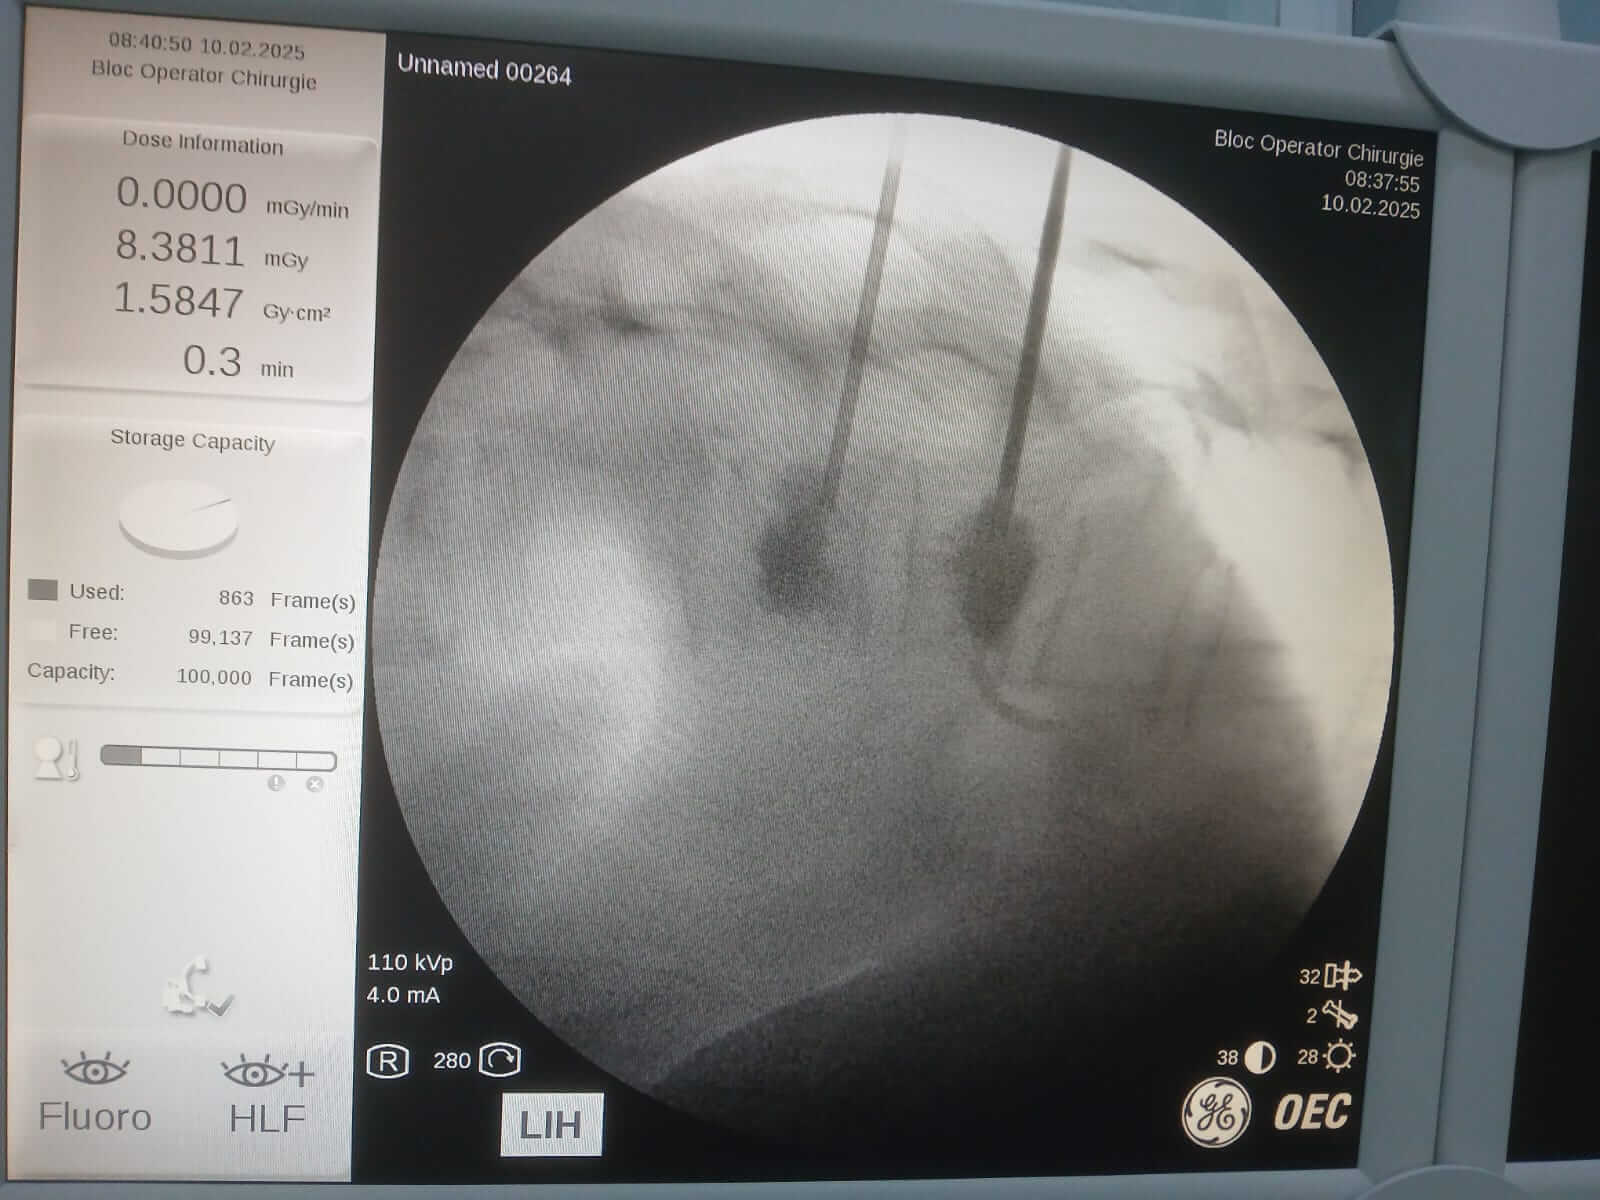

În data de 10 februarie 2025, la Spitalul Județean de Urgență Buzău a avut loc o intervenție neurochirurgicală în premieră. Este vorba despre o intervenție de vertebroplastie percutană, sub control radiologic.

În urma investigațiilor efectuate, au fost identificate două fracturi, prin tasare ale corpurilor vertebrale toracale T11 și T12, fiind nevoie urgent de intervenție neurochirurgicală. După ce a aflat diagnosticul, pacienta și-a exprimat acordul de a efectua intervenția în unitatea noastră.

În premieră la nivelul județului Buzău, s-a intervenit neurochirurgical prin procedura denumită „vertebroplastie percutană sub control radiologic”. Operația a durat 30 de minute iar pacienta s-a recuperat complet, cu externare în aceeași zi, post procedural.